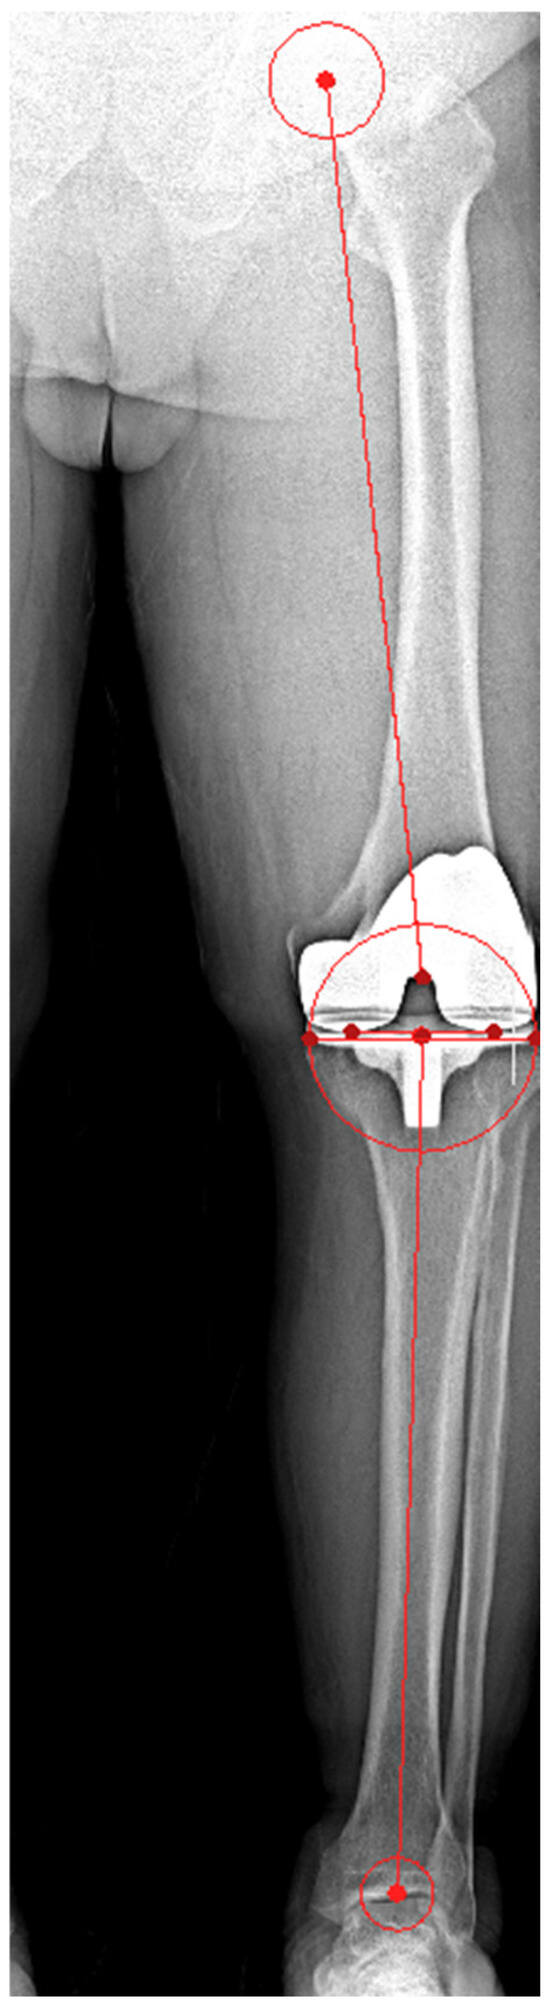

| HKA angle | |||

| Value (°) | 59.2 ± 14.2 | 47.6 ± 12.4 | 0.004 |

| Outlier (n, %) | 119 (36.3) | 23 (7) | <0.001 |

| FCA | |||

| Value (°) | 89.7 ± 1.9 | 89.8 ± 1.5 | 0.453 |

| Outlier (n, %) | 39 (11.9) | 14 (4.3) | 0.002 |

| TCA | |||

| Value (°) | 89.1 ± 1.9 | 89.7 ± 1.6 | <0.001 |

| Outlier (n, %) | 42 (12.8) | 23 (7) | 0.03 |